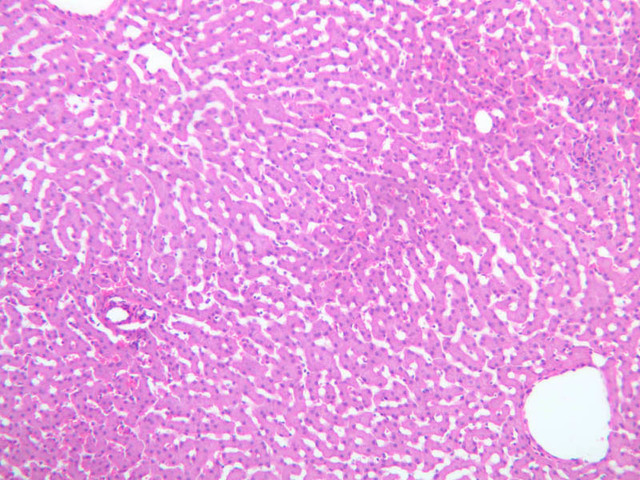

Examine the H&E-stained sections of liver (slides B-29 [10x, 20x, 40x-labeled] [2.5x-labeled, 10x, 20x, 40x] [10x-labeled, 20x, 40x-labeled] and B-30 [2.5x, 10x-labeled, 20x]). At low power, identify the connective tissue capsule (Glisson’s capsule), central veins and portal triads (portal canals). Note that the cells of the liver parenchyma (hepatocytes) appear as cords--more accurately, plates--of cells that radiate out from the central veins and partially enclose blood spaces known as hepatic sinusoids. Note that the plates of hepatocytes appear to branch and fuse and that, as a rule, they are only one or two cells thick. Do you see any binucleate hepatocytes?

Using the 10X (B-29, B-30)and 40X (B-29) objectives, examine several portal triads, noting the variable number of profiles of hepatic artery, portal vein and bile duct that comprise the portal triad. Near the boundary between adjacent lobules, try to find some of the small elements of the bile duct system known as canals of Hering.